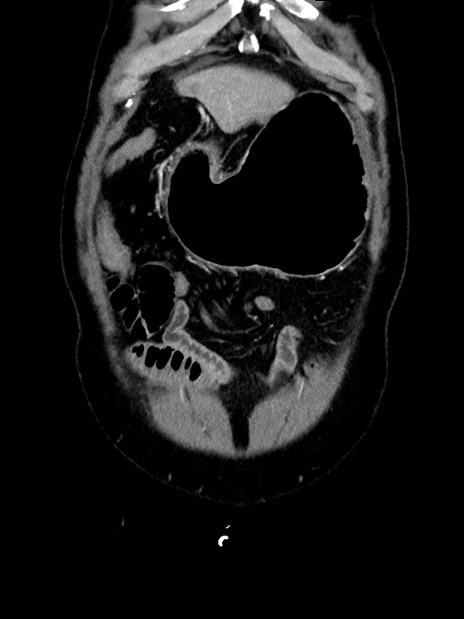

症例35(冠状断像)

【症例】70歳代 男性

【主訴】腹部膨満、嘔吐

【現病歴】昨日より腹部膨満感出現。本日増悪し、仙痛出現。嘔吐あり、受診。

【既往歴】糖尿病、胆摘後

【身体所見】BP 149/80mmHg、HR 74/min、BT 35.9℃、腹部:膨満、軟、圧痛なし。腸雑音減弱あり。上腹部正中切開瘢痕あり。

【データ】WBC 13500、CRP 1.72